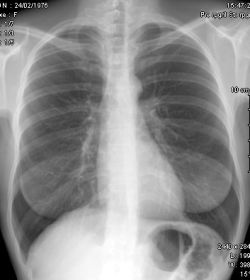

Les radiographies sont fréquemment requises entre autres, pour la recherche d'une fracture dans le cadre d'un traumatisme, pour l'étude des poumons au cours d'une radiographie thoracique ou pour visualiser l'abdomen au cours d'un cliché appelé ASP pour Abdomen Sans Préparation.